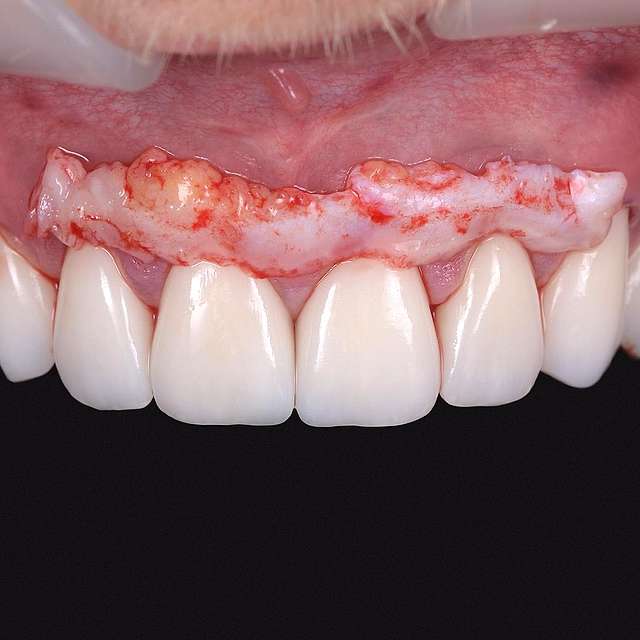

Grefa gingivala este o micro-chirurgie prin care se transplanteaza o mica bucata de tesut moale - gingie sau tesut conjuctiv (stratul intern al gingiei) pentru a acoperi un defect gingival. De obicei, acest tip de interventie este necesar pentru augmentarea implanturilor dentare, sau pentru a acoperi defecte cauzate de traume sau de afectiuni parodontale.Grefele se recolteaza din zona molarului de minte, sau de pe palat, si sunt transplantate in zona afectata.

Acesta interventie este una foarte delicata, lamele folosite pentru a efectua procedura sunt aceleasi folosite in oftalmologie, iar firele de sutura sunt si ele foarte fine. Firele se indeparteaza dupa 7-14 zile, in functie de caz, cand are loc vindecarea primara. Maturarea grefei dureaza aproximativ 90 zile, de aceea in momentul inserarii implanturilor preferam sa facem si grefa de tesut, pentru a sincroniza timpii de vindecare si ambelor proceduri.